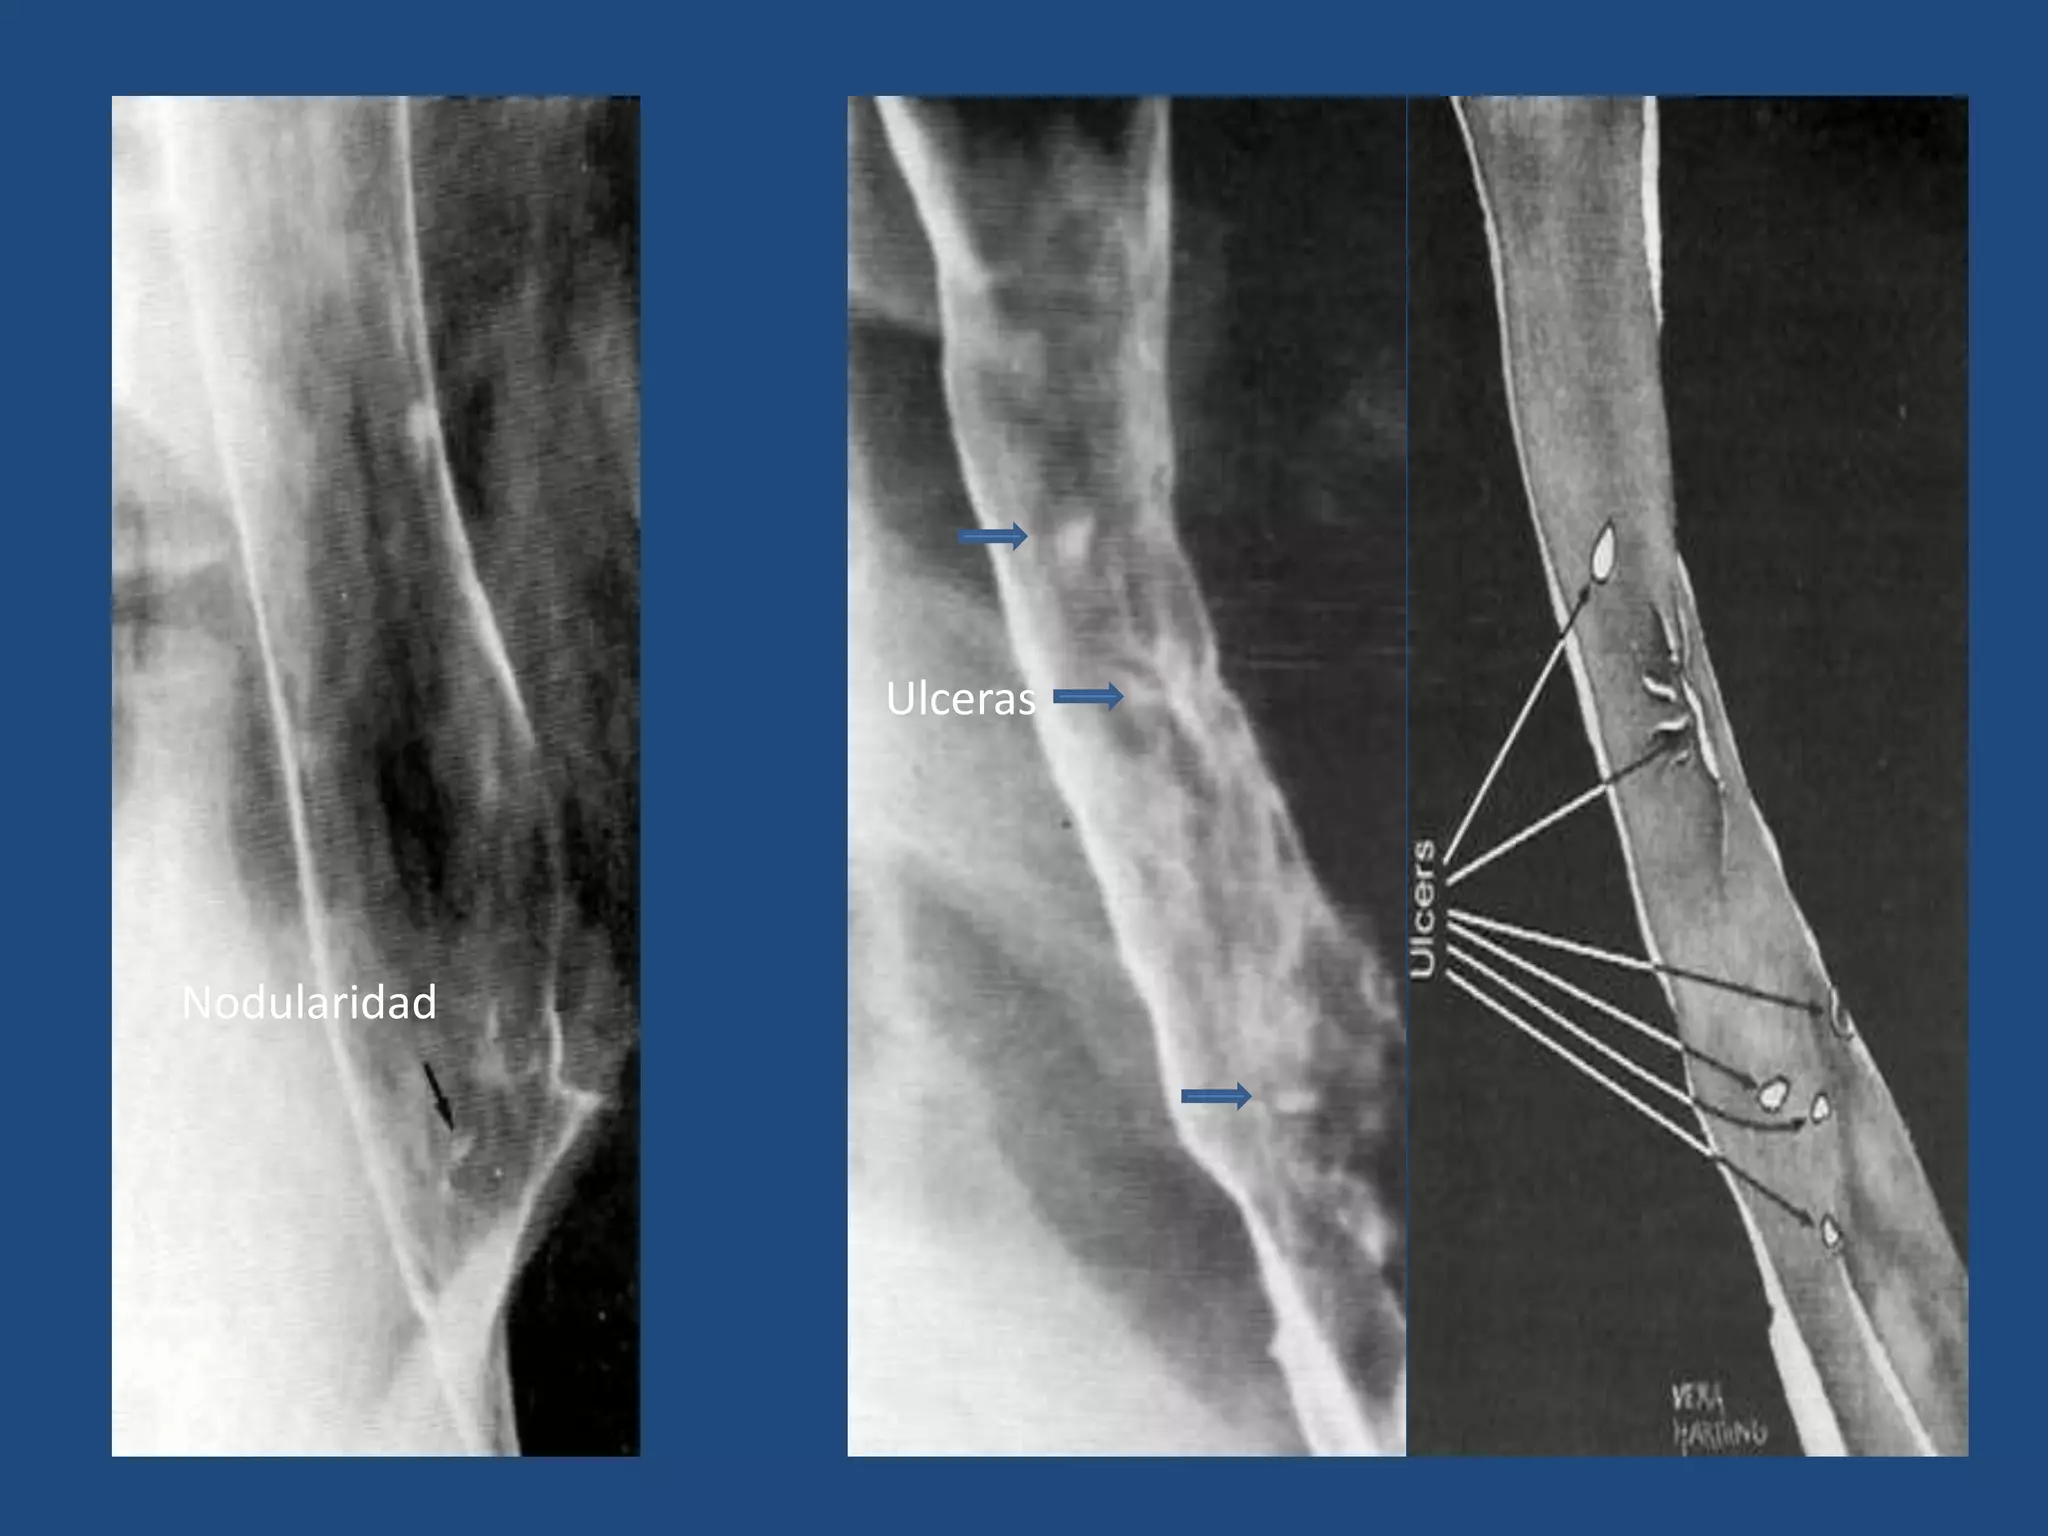

• ESOFAGITIS:

Hallazgos radiológicos:

Ausencia de peristaltismo

Irregularidad o nodularidad de la pared

Limitación de la distensibilidad.

Ulceras

HALLAZGOS GENERALES

Nodularidad

“empedrado”

Ulcera ovoidea

Ulcera con edema

Estenosis